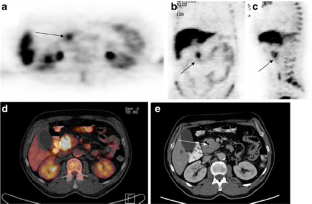

Fig. 1